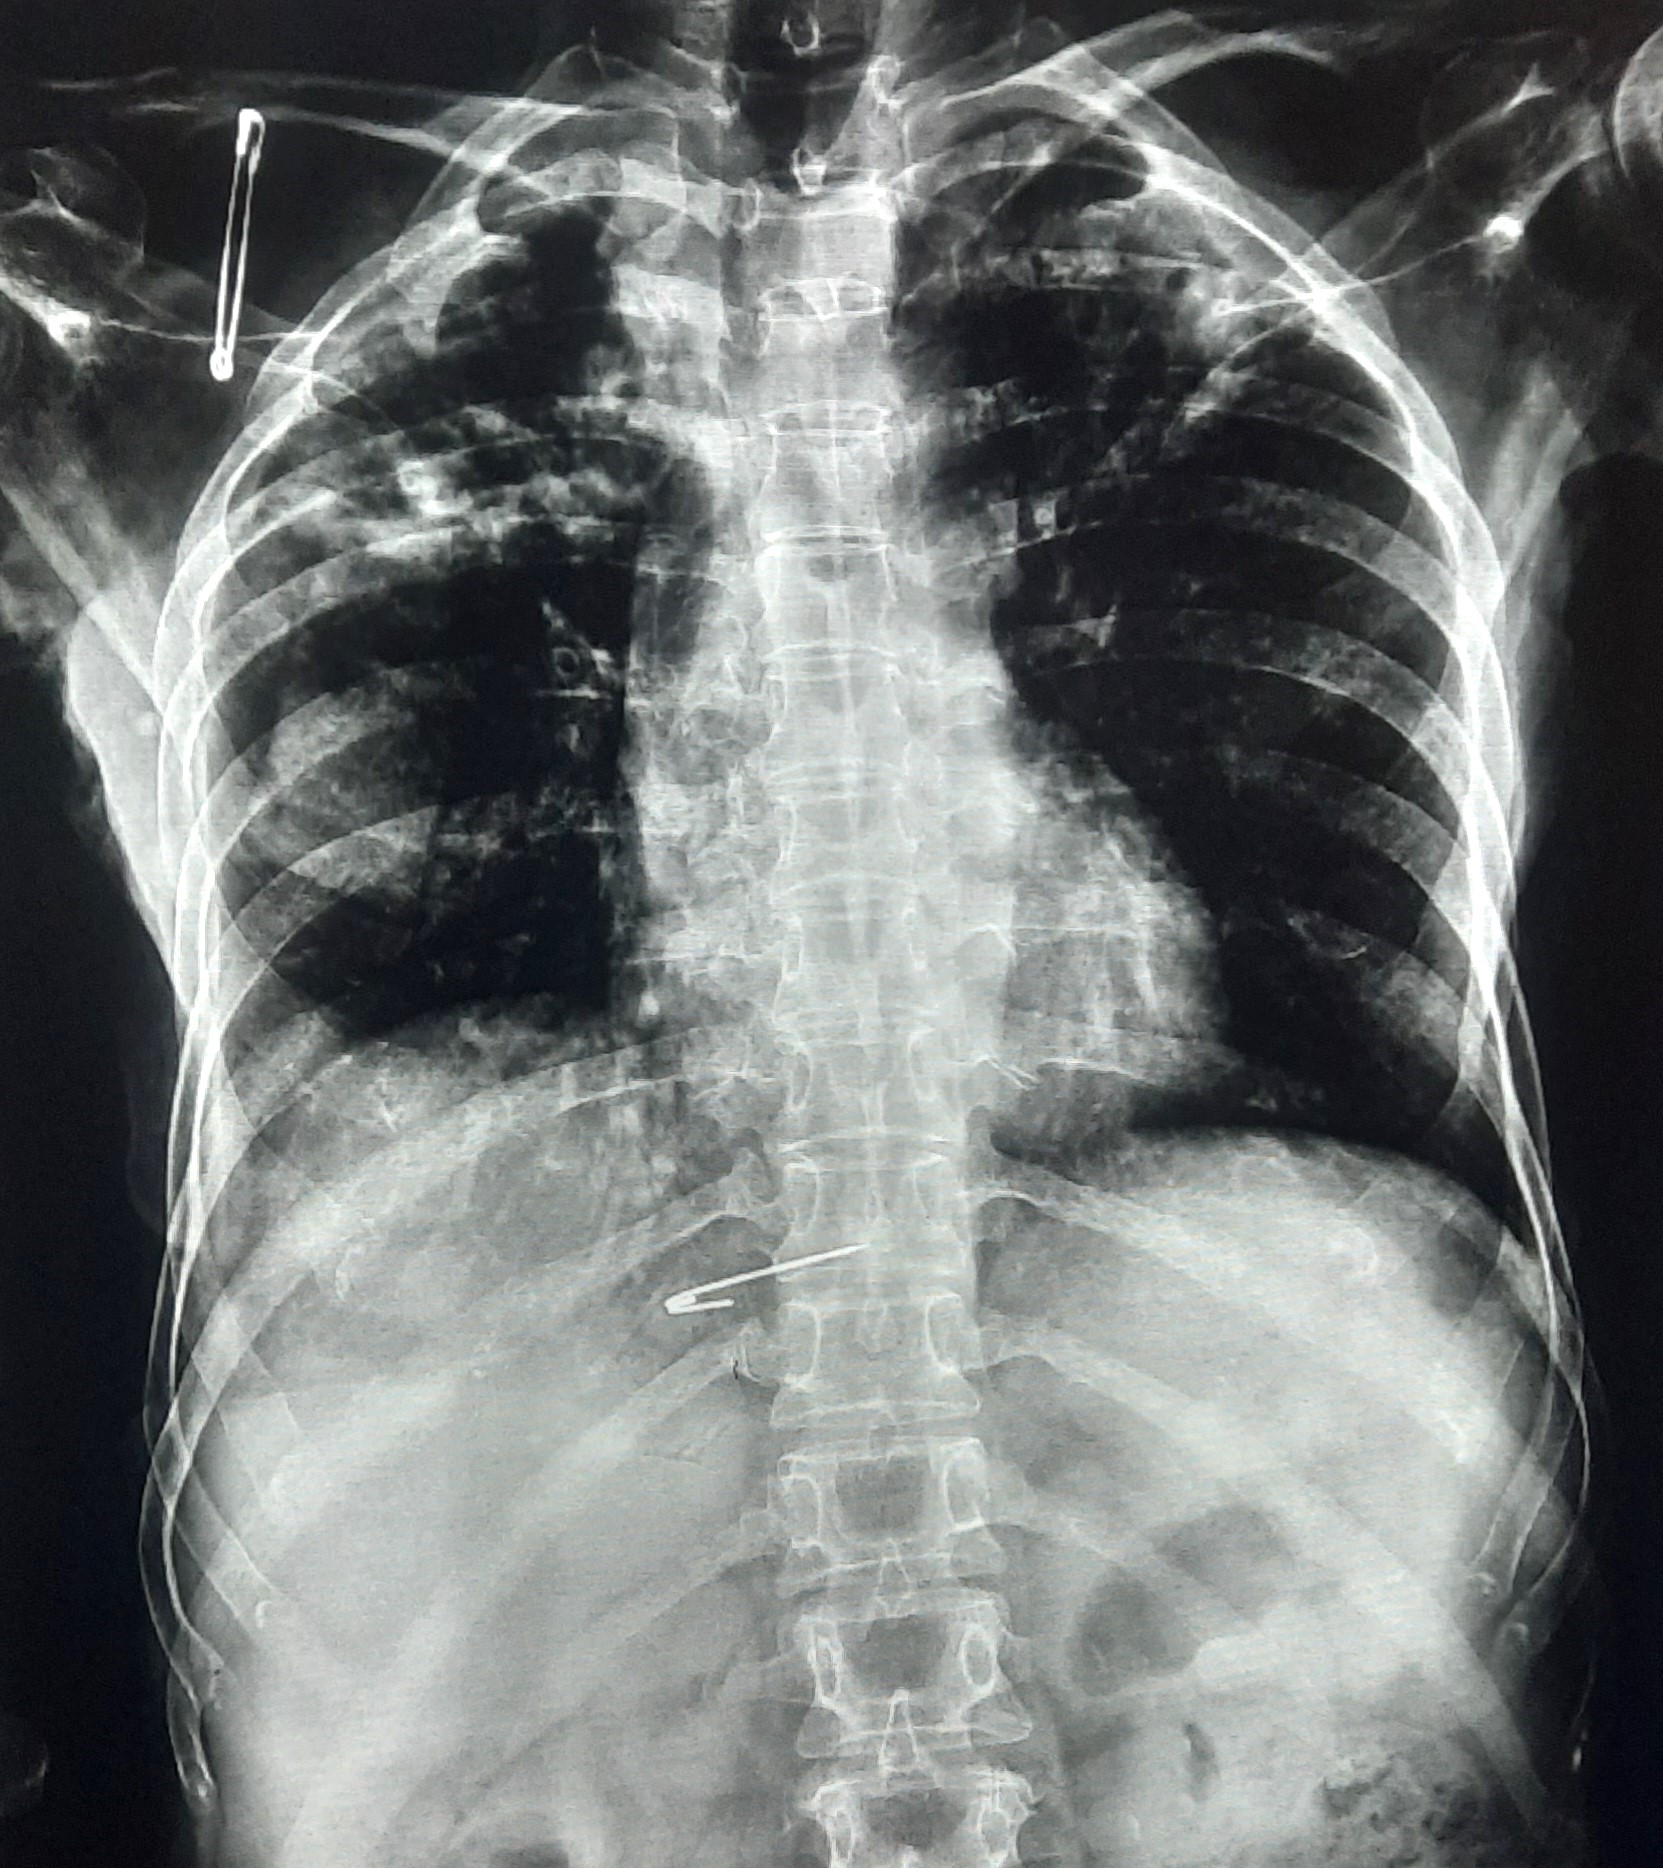

| 149 | IGGMC, Nagpur, Nagpur | P2 | 29-4323 | Samina Parveen | Consent taken on Paper | 30 Yrs. |

Provisional Diag : Bilateral Tubercular Pleural Effusion

Final Diag : Bilateral Tubercular Pleural Effusion With Right Sided Pigtail Infiltration |

TB Case (Confirmed) | Bilateral CP Angle Blunting With Bilateral Homogenous Opacity Left Zone With Pigtail Right Pleural Effusion | Abnormality visible on x-ray |